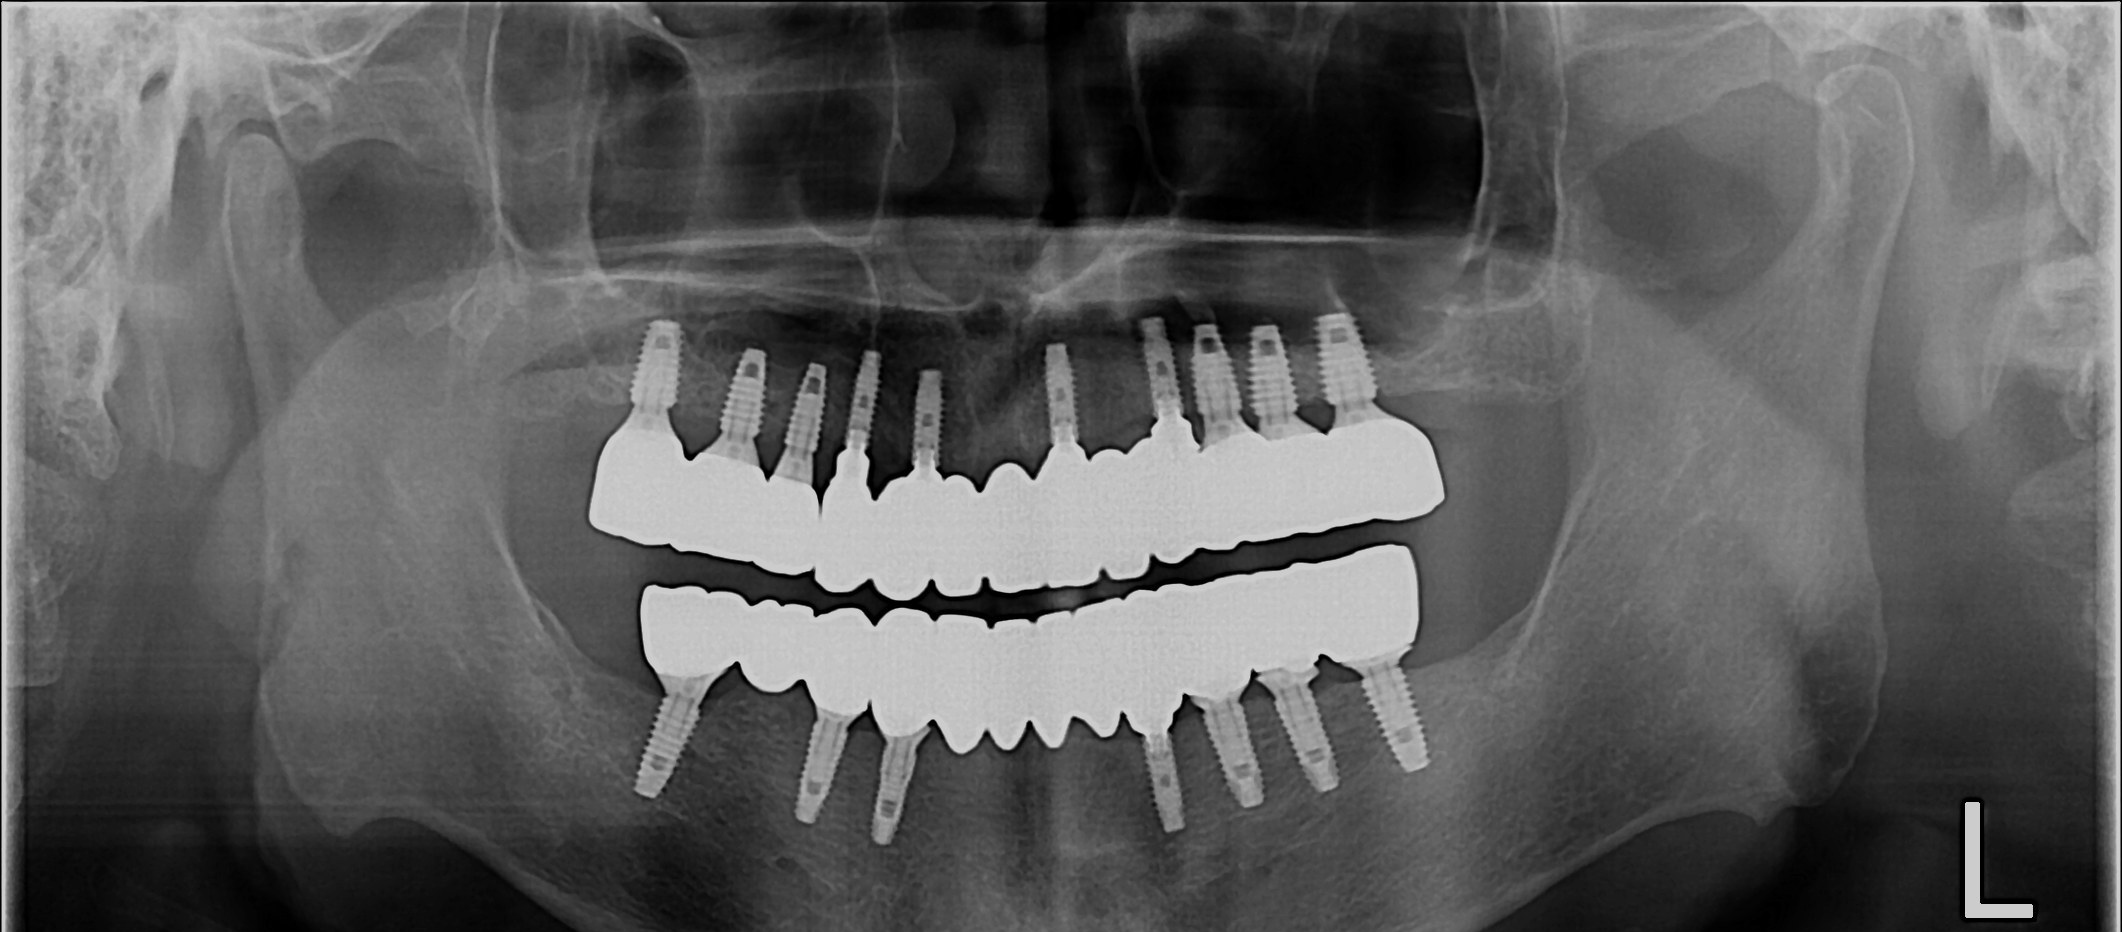

무치악 임플란트 회복

After

무치악 임플란트 회복 Full Mouth Rehabilitation